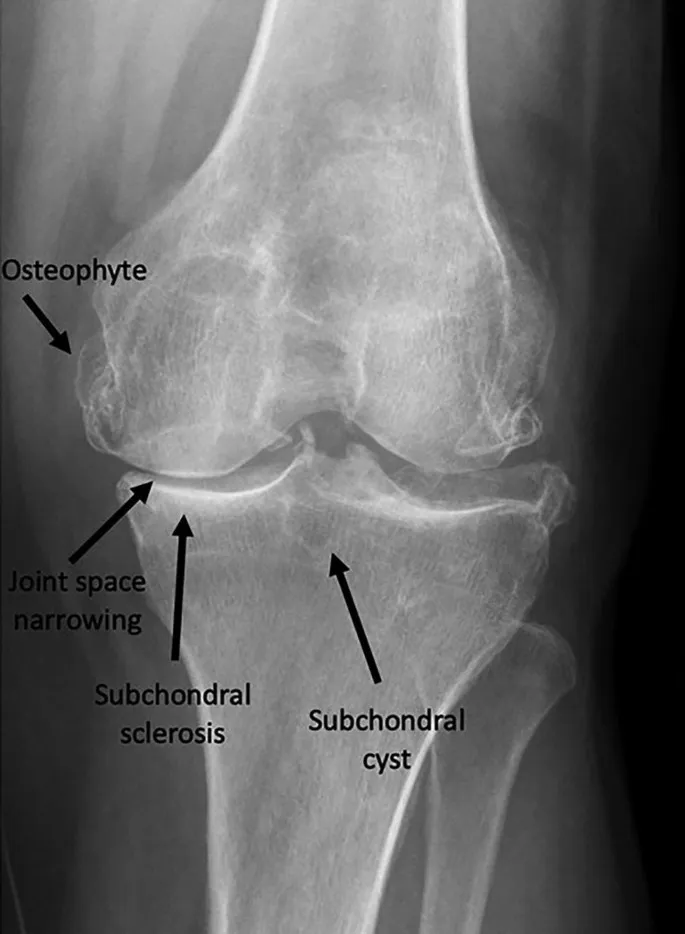

- Imaging (X-ray):

- 📌 JOSS Mnemonic:

- Joint space narrowing (asymmetric)

- Osteophytes

- Subchondral sclerosis

- Subchondral cysts

- Classic X-ray findings: asymmetric joint space narrowing, osteophytes, subchondral sclerosis, and cysts.